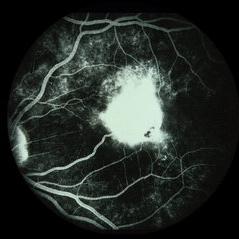

Toxocara Granuloma

Toxocara Granuloma

Feb 25 2013 by Henry J. Kaplan, MD

Toxocara granuloma of ON, late stage F/A. #3 Late hyperfluorescence in the granuloma due to staining.

Condition/keywords: ocular toxoplasmosis, toxocara granuloma, toxocariasis

Toxocara Granuloma

Toxocara Granuloma

Feb 25 2013 by Henry J. Kaplan, MD

Toxocara granuloma of optic nerve; F/A.

Condition/keywords: ocular toxoplasmosis, toxocara granuloma, toxocariasis